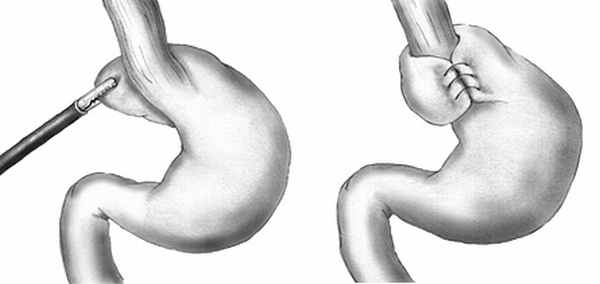

Фундопликация по Ниссену (англ. Nissen fundoplication) — антирефлюксная операция, заключающаяся в том, что дно желудка обворачивают вокруг пищевода, создавая манжетку, препятствующая забросу желудочного содержимого в пищевод. Впервые антирефлюксная операция — фундопликация была проведена Рудольфом Ниссеном 1955 году, предложившим формировать муфту из верхней части дна желудка состоявшую в 360-градусной пликации 5-сантиметровой манжетки вокруг нижней части пищевода (Васнёв О.С.). При проведении фундопликации восстанавливается не только анатомическое строение, но и функциональное состояние нижнего пищеводного сфинктера: восстанавливается тонус, уменьшается количество преходящих расслаблений при растяжении желудка, улучшается его опорожнение.

Рис.1. Общая схема фундопликации по Ниссену

Фундопликация по Ниссену может выполняться как лапароскопически, так и открытым способом. Фундопликация по Ниссену, включая её модификации и в настоящее время считается «золотым стандартом» антирефлюксной хирургии.

Классический способ блокирования рефлюкса путем обертывания вокруг пищевода желудочного дна. В результате создается специфический манжет, исключающий заброс кислоты из желудка в пищевод.

Фундопликация по Ниссену в нашей клинике обычно выполняется лапароскопически — через три небольших разреза, под общим наркозом. Хирург оборачивает дно желудка вокруг пищевода и создает манжетку, которая препятствует забросу желудочного содержимого в пищевод.